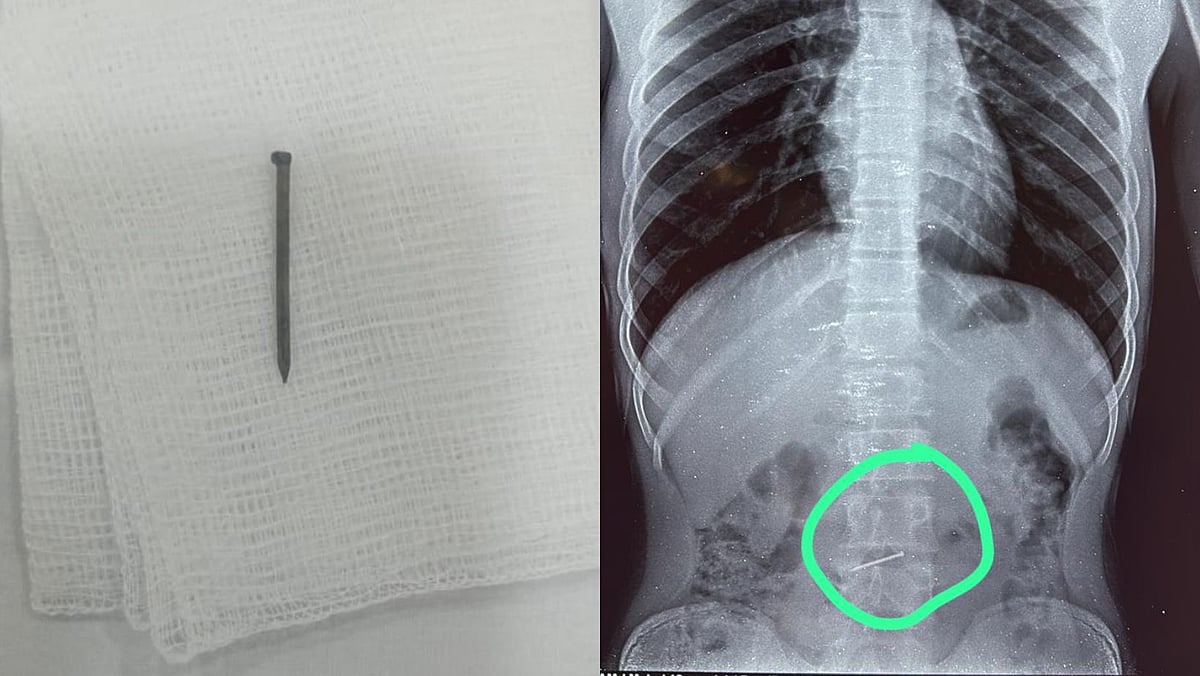

The X-ray revealed a nail in the upper part of his intestine. The sharp object posed a serious risk of internal injury. Considering the criticality of the condition, the team of doctors led by Dr Prasad Bhate, HOD and Senior Consultant – Gastroenterology, Manipal Hospital, swiftly planned to perform an emergency endoscopy procedure to remove the nail.

The patient was brought to the hospital two hours after swallowing the nail. It was easy to find the foreign object via endoscopy because the patient had not eaten anything. The nail was found at the junction of the small intestine, making its removal critical to prevent injury to the internal organs. The nail was gently removed from the body without any surgical procedure.